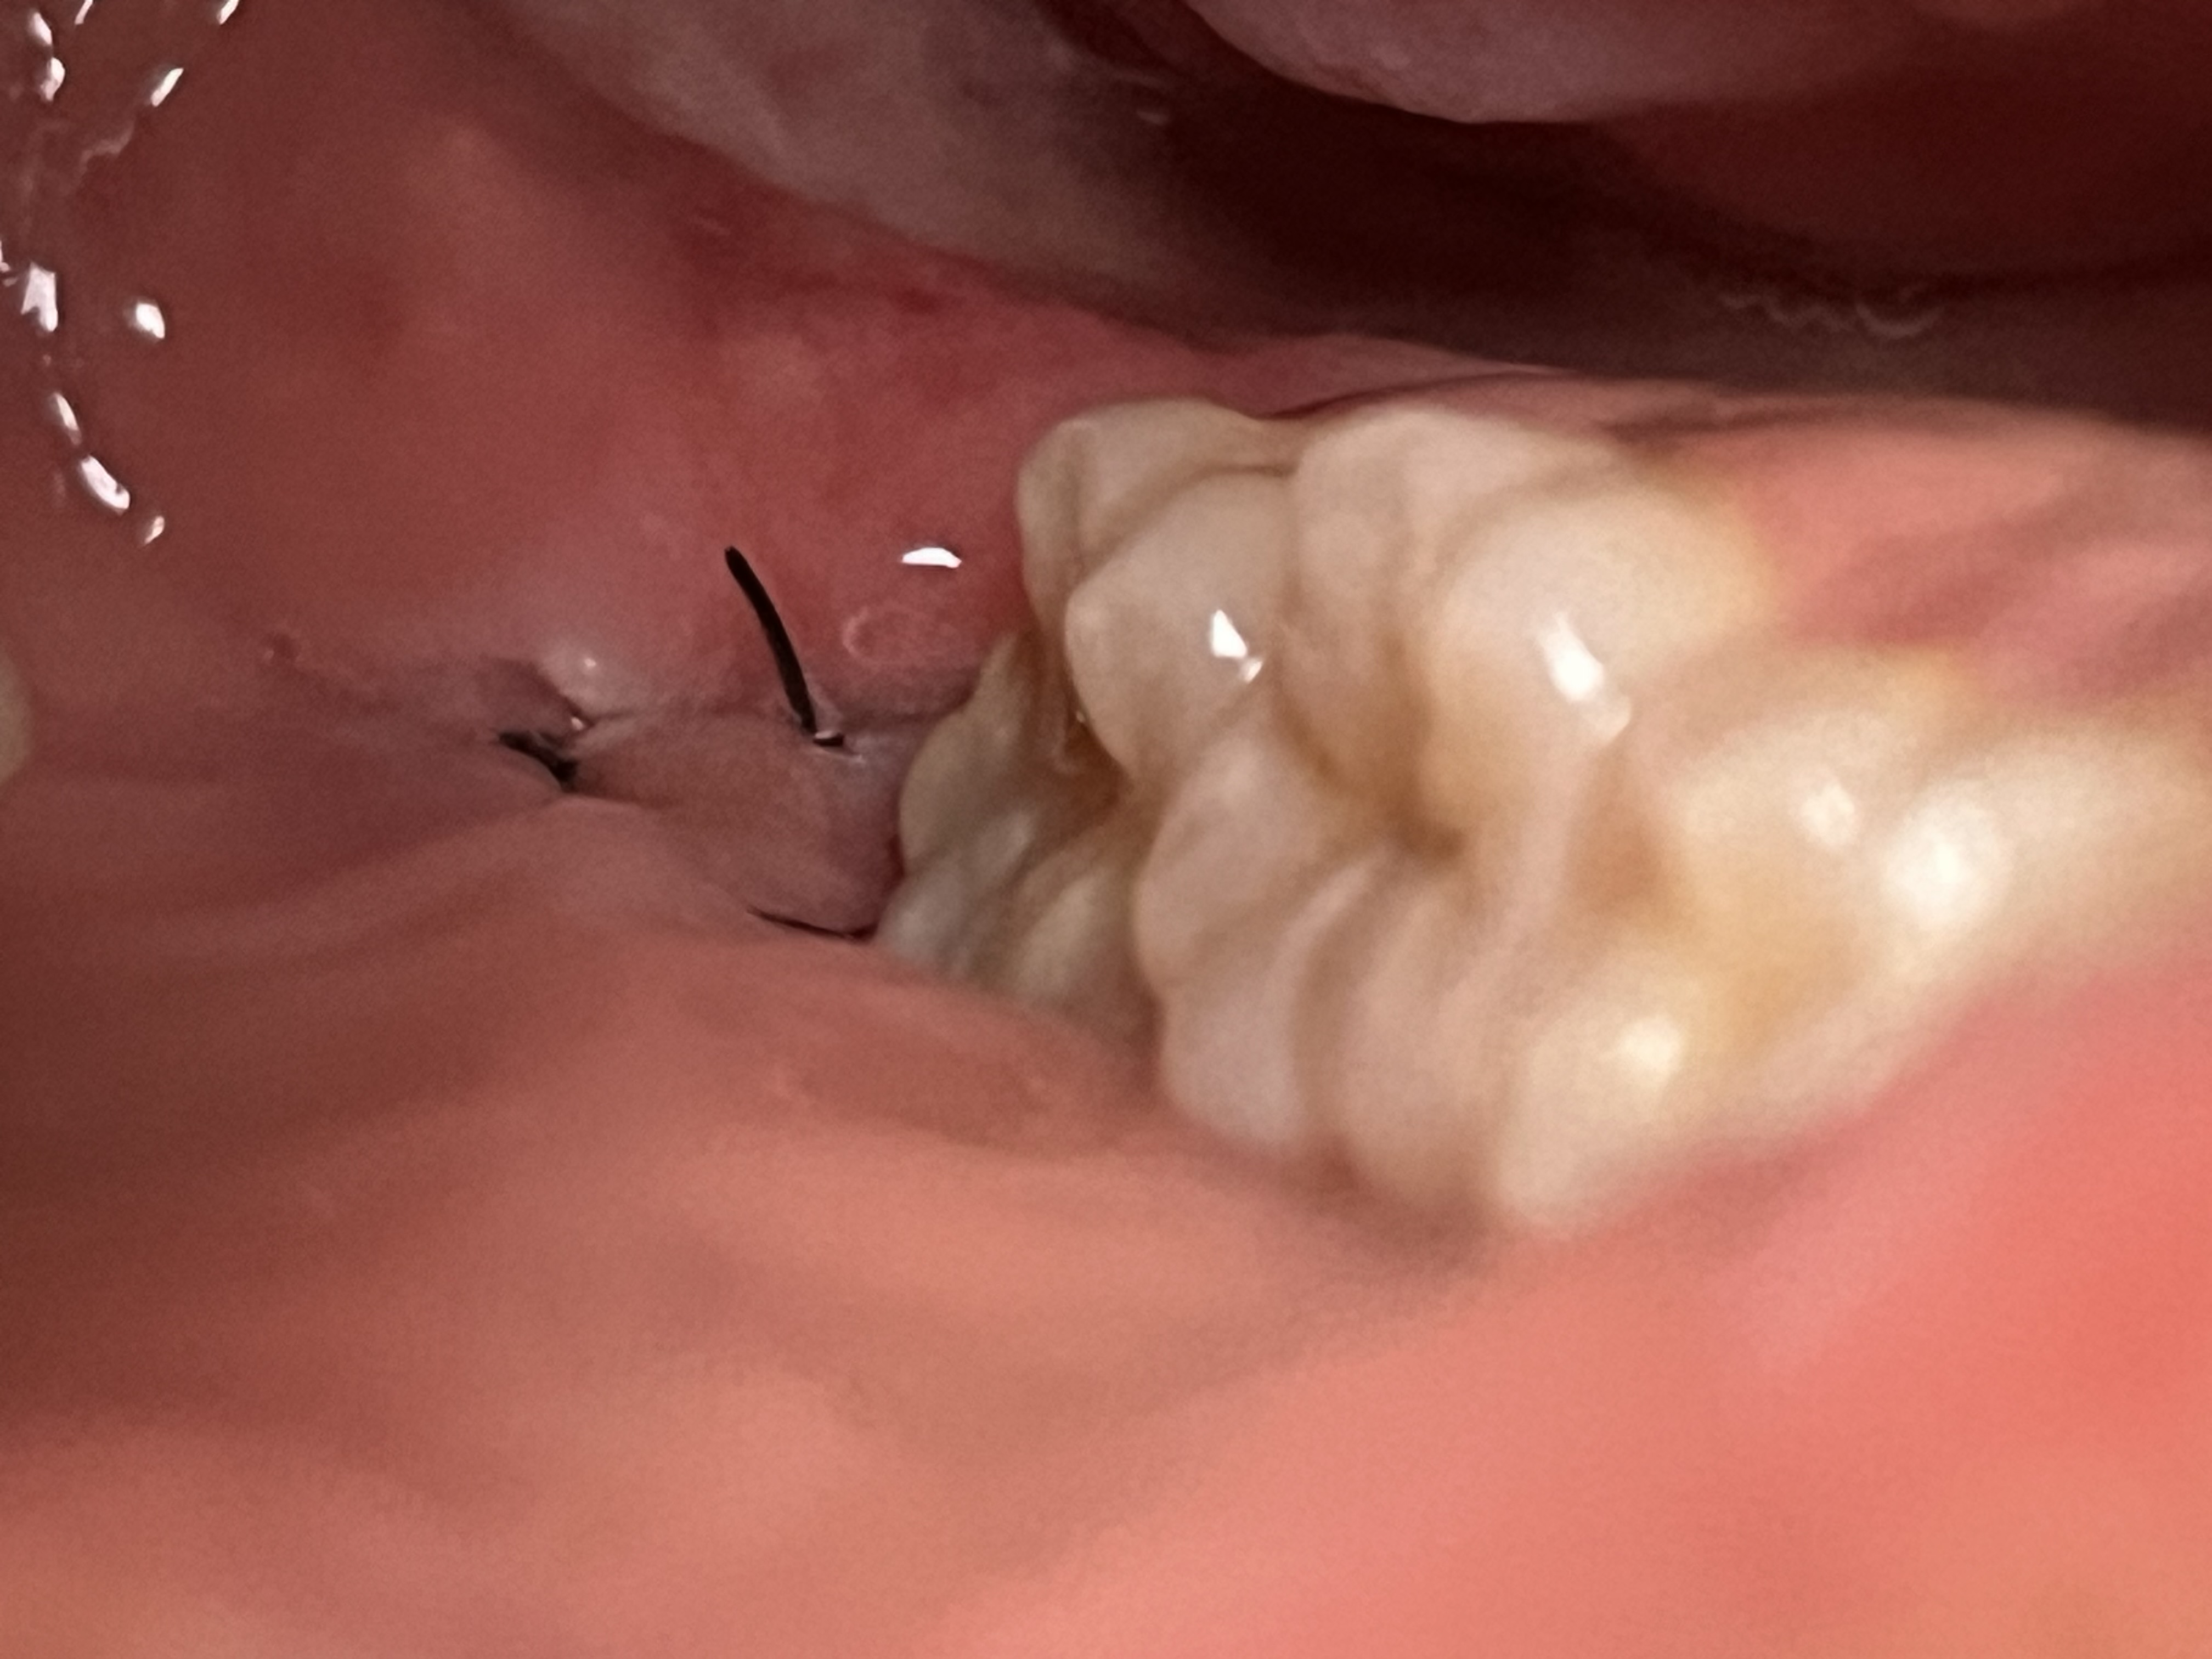

親知らず抜歯後、縫合部分に空いている隙間は埋まりますか?